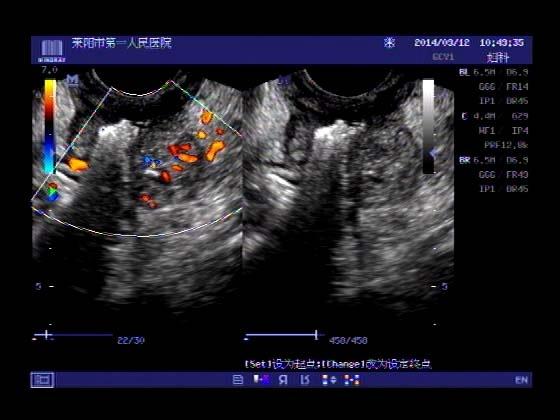

超声入门贴353-----直肠癌伴肝转移

女,66岁